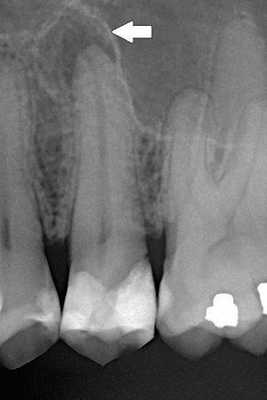

Диагноз перикоронарита ставится стоматологом на основании клинических проявлений, жалоб пациента и инструментального осмотра. Иногда для определения направляющей роста проводят рентгенологическое исследование. Лечение перикоронарита направлено на предотвращение осложнений, а выбор лечебной методики зависит от особенностей течения заболевания и от состояния пациента. Если при перикоронарите воспалительный отек выражен значительно или отмечается сведение челюстей, то показана тригеминосимпатическая блокада. При течении без осложнений карман под капюшоном промывают слабым раствором фурацилина или перманганата калия.

Экстракция зуба мудрости показана в том случае, если он находится в положении, при котором прорезывание невозможно. Это подтверждается рентгенологическим исследованием, удаление зуба проводят после снятия острых симптомов перикоронарита, после экстракции лунка зуба очищается, и накладываются швы. Так как зуб мудрости не несет функциональной нагрузки, то при перикоронарите трудно поддающемуся лечению, зуб рекомендовано удалить. Рецидивирующий перикоронарит излечивается только после экстракции зуба мудрости.

Диагноз перикоронит зуба мудрости может поставить только лечащий врач-стоматолог на основании жалоб пациента и осмотра его ротовой полости. Иногда специалист направляет пациента на рентген, чтобы определить положение растущего зуба, степень искривления ряда и оценить вовлечение костных структур в воспаление.

Для визуализации неправильно расположенного зуба может потребоваться прицельная рентгенография, компьютерная томография или ортопантомография.

Поставить точный диагноз может врач-стоматолог. Обязательной является рентгенография — прицельный снимок поможет точно оценить состояние тканей, положение прорезывающегося зуба в челюсти, степень распространения воспалительного процесса, а также исключить заболевания с похожими симптомами.